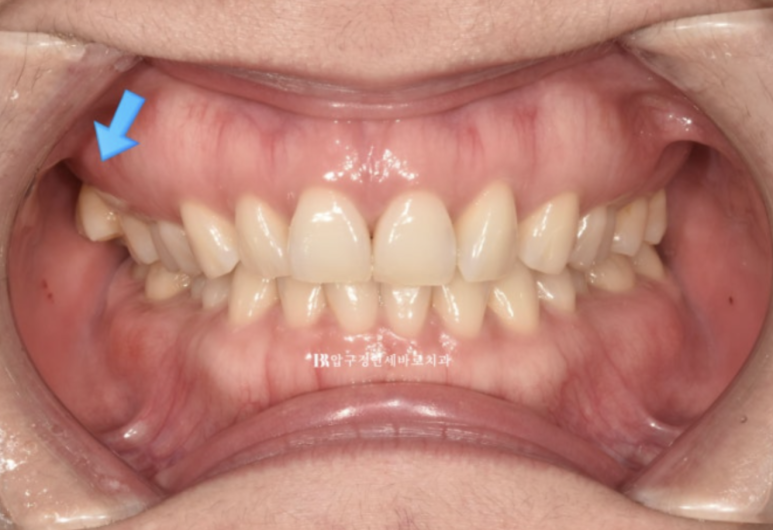

23.07

오른쪽 맨 뒤 큰 어금니의 가위교합이 보이고 왼쪽은 송곳니와 앞니 벌어진 공간이 보입니다.

인비절라인 라이트로 이 모든 것을 해결하고 치료에 들어갑니다.